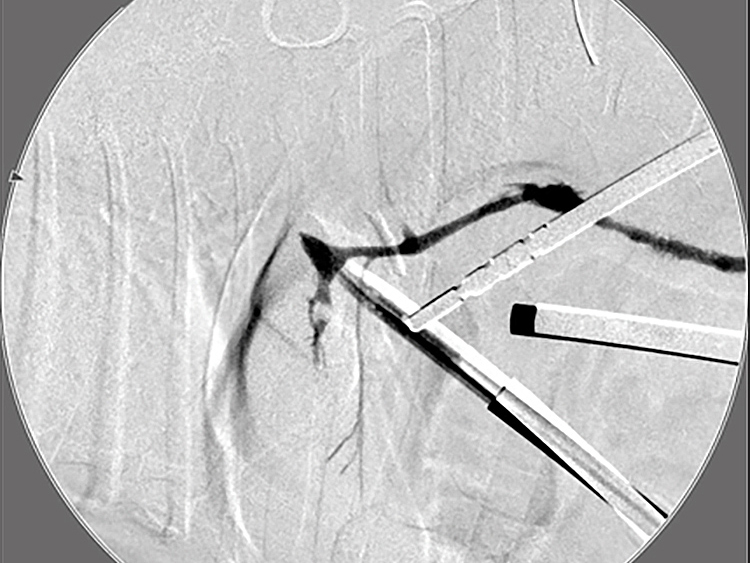

胆嚢の通路がちゃんと開通しているのか調べるために造影検査をしています。 この処置をすることで洗浄の効果と詰まりを確認することができます。

総胆洗浄をして詰まりがないかまずは確認します。

きれいに開通していました。鉗子が大きく感じますが体が小さいので大きく見えます。

詰まりがないかを透視で確認しています。